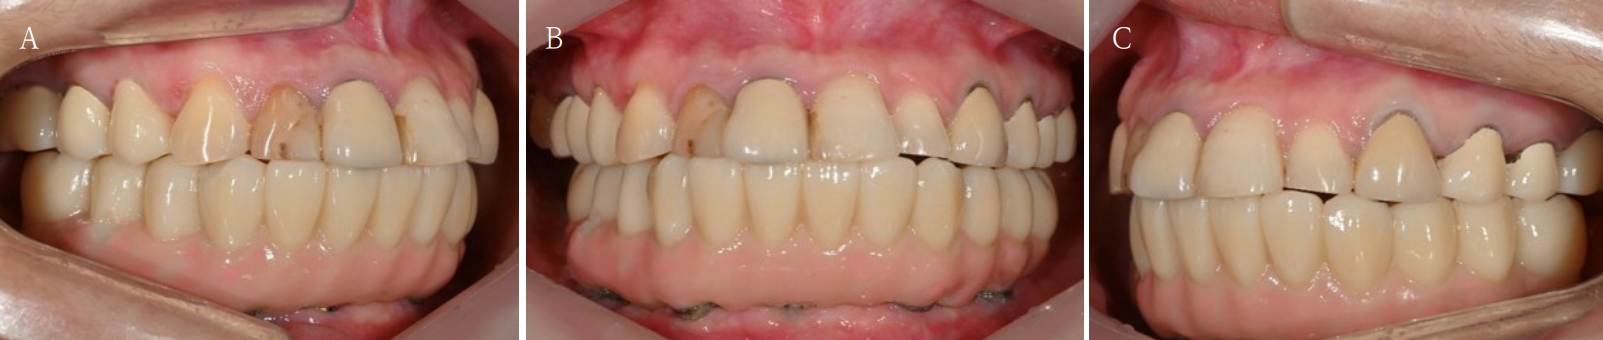

Fig. 5.

The patient is satisfied with the occlusion and vertical dimension of newly fabricated temporary denture. A. Right side view. B. Frontal view. C. Left side view.

jkda-2025-63-7-001f5.jpg